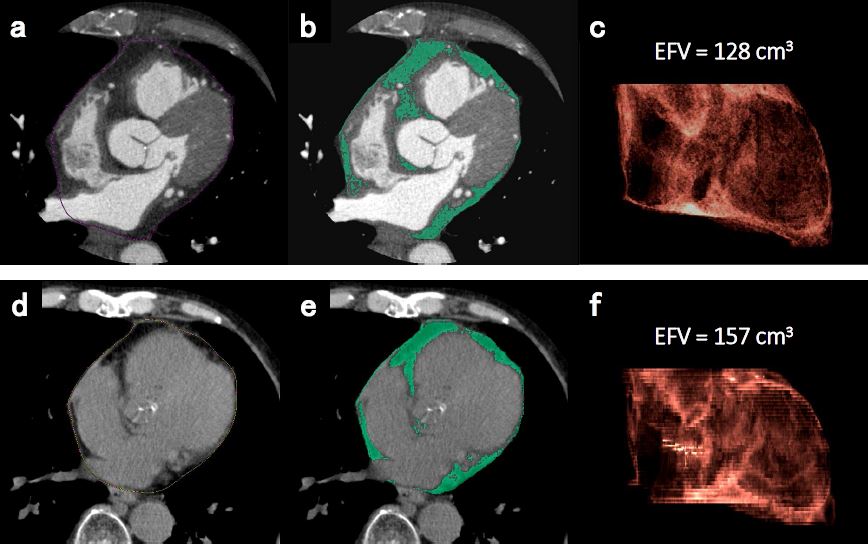

The amount of epicardial fat can be estimated on regular CT without gating. Measurements are robust. It is related to the presence of coronary artery disease.

Article: Epicardial fat volume measured on nongated chest CT is a predictor of coronary artery disease